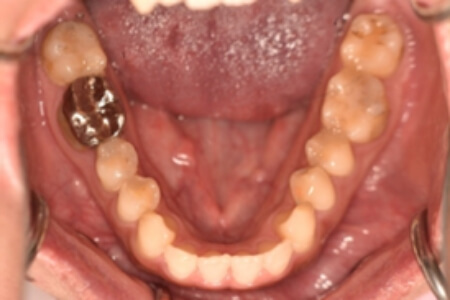

| 治療内容の詳細 | 初診時26歳の男性で、受け口を気にされ来院されました。 検査の結果、下顎前突、上顎前歯部叢生および上顎側切歯反対咬合を伴うアングルⅢ級不正咬合と診断しました。 先ず、前期治療として、リンガルアーチを使用し、上顎中切歯を前方へ移動させ、反対咬合の改善を行いました。 その後、マウスピース型矯正装置(インビザライン)で配列を行いました。 治療期間としては1年8か月でした。 |